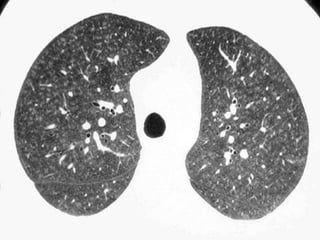

Lymphangioleiomyomatosis (LAM)

HRCT Morphology

Thin-walled cysts (2mm - 5cm)

Uniform in size / rarely confluent

Homogeneous distribution

Chylous pleural effusion

Lymphadenopathy

in young women